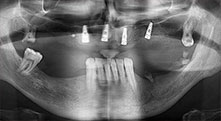

Bratu: We routinely use the instruments for harvesting bone blocks and splitting alveolar ridges. We also use the Piezomed B6/B7 for osteotomy of impacted teeth and removing failed implants. All indications that require deep, clean cuts.

Bratu: We prefer to harvest bone from the external oblique ridge of the posterior mandible, not from the interforaminal region. After the soft-tissue incision, we use the new saws to define the amount of bone to harvest. With this approach, we also use them for the entire preparation in almost 80% of cases. We may also use other piezo instruments and then at the end a chisel to mobilize the block. We find that this is a very effective surgical technique.

Could you give us a few surgical tips and tricks from your hospital?

Bratu: We like to use the sandwich technique for augmentation in the lateral mandible. A bone cover is prepared with the piezo saw and the crestal fragment is fixed with microscrews. We place a mixture of autologous bone and xenogenic bone replacement material in between. This works very reliably. You should always ensure sufficiently dimensioned vertical cuts when splitting the alveolar ridge in the mandible. Otherwise the bone may fracture easily.